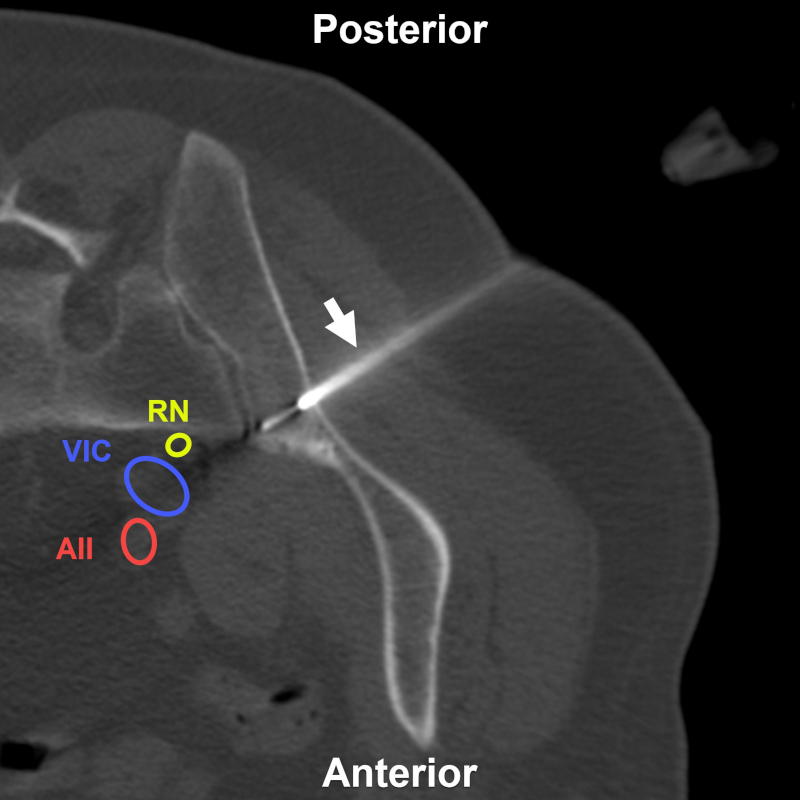

Mujer de 78 años con pérdida de peso significativa y lesión escasamente visible por TC e hipercaptante en la tomografía por emisión de positrones. BP directa transilíaca posterior (flecha) bajo TC. Estructuras a evitar: RN: raíz nerviosa de L5; AIC: arteria ilíaca común; VIC: vena ilíaca común; NF: nervio femoral; NFC: nervio femorocutáneo. Aguja utilizada: Jamshidi 11 G. Diagnóstico final: infiltración secundaria por carcinoma.